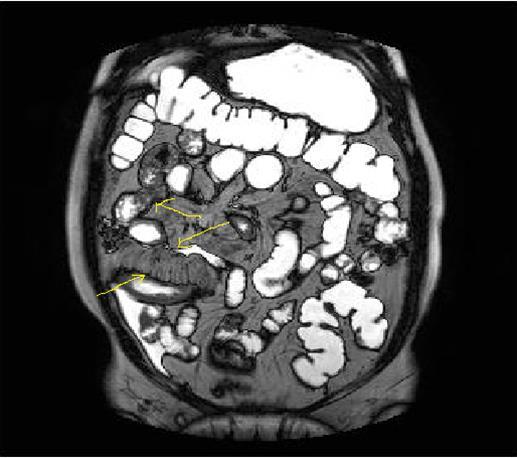

Mucosal irregularities and ulcerations, strictures and fistulas at chronic stage can also be visualized by enteroclysis3, 4, 14, 15, 22 (Figure 3a-b-c).Clinical signs of Crohn’s disease are; Abdominal ache, diarrhea, fever, loss of weight, malnutrition, hemorrhage and fistulas, its extra-intestinal manifestations are: Arthritis, iridocyclitis, erthytema nodosum, aftoz stomatitis, cholelithiasis, primary sclerosing cholangitis and ankylosing spondylitis8, 9, 10, 11, 12, 13, 14, 15, 16,20, 21, 22.In the differential diagnosis; Ulcerative colitis(UC), ischemic colitis(IC), infectious-fungal and tuberculous(Tbc) enteritis, radiation enteritis, Lymphoma, Behcet’s disease have to be thought5, 6, 7,18, 19, 20, 21 . UC involves the entire colon, small intestine involvement is extremely rare, it tends to involve only the mucosal part of bowel with continuous pattern and skip lesions-transmural pattern of Crohn’s disease involvement can never be seen in UC, fistulization and abscess formations are not evident, terminal ileum involvement of UC is named as backwash ileitis, UC is a pre-malignant inflammatory disease which often causes rectal adenocarcinoma, Malignant transformation of Crohn’s disease is extremely rare 6, 8, 10, 14, 18, 19

Figure 3a-3b-3c.Diffuse mucosal involvement and extreme luminal narrowing in the terminal ileum due to Crohn’s disease on T2W coronal sequence after OCA administration, stricture and string sign near ileo-ceccal valve in Figure 3b.